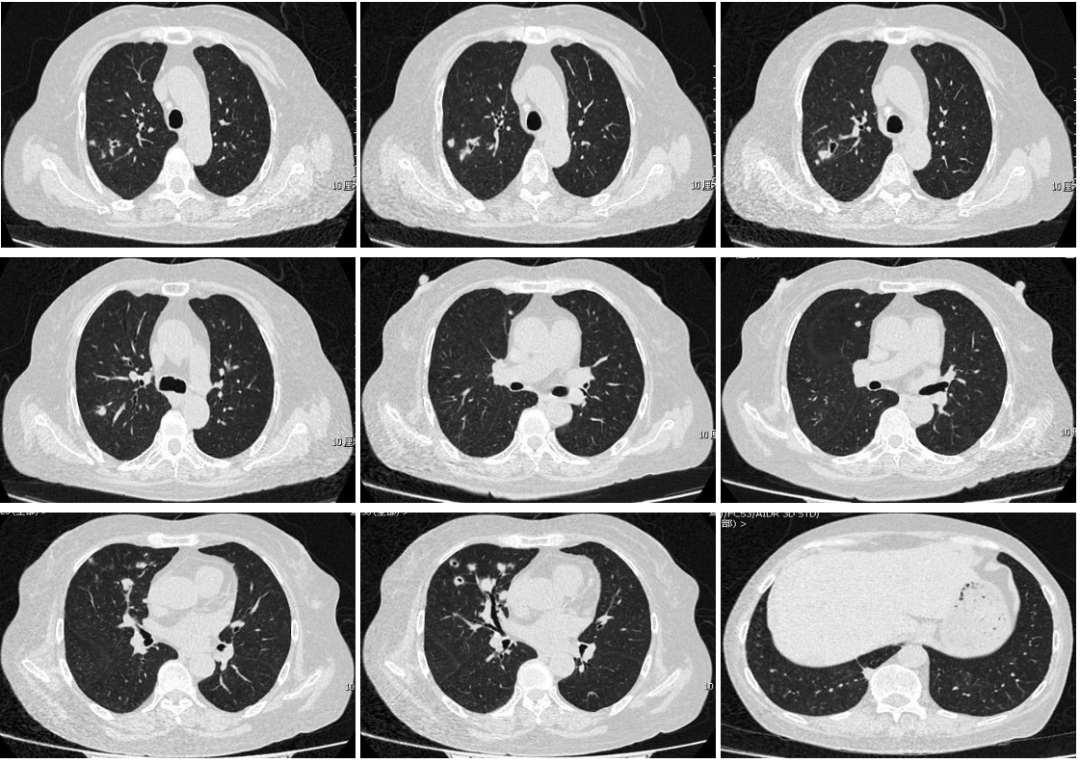

患者男,32岁,患者于2016-8在治疗急性白血病过程中出现发热,咳嗽、咳痰,最高体温39.5°C,给予头孢克肟抗感染体温未见明显下降,后改为亚胺培南西司他丁钠(0.5 g q6 h)联合阿米卡星(0.4 g qd)治疗,患者体温于2016-8-19降至正常。

患者2016-8-25再次出现发热,体温37.8°C,因患者合并粒细胞缺乏,不除外真菌感染。患者以肺部感染入院。

胸部CT示右上肺团块状高密度影,伴有晕征。

支气管镜下可见右上叶支气管开口可见大量灰黄色脓性分泌物附着管壁,向右上管腔生长,完全阻塞管口,支气管不能进入,坏死物质韧,拉扯不断。

我们取出了很少的分泌物和组织,立刻送检实验室,看到镜下有一些分隔形成的偏细长型的分枝菌丝的表现,这就是真菌感染。在培养下,我们考虑为真菌,主要是毛霉感染。经过标准的两性霉素B治疗,慢慢得到有效吸收。